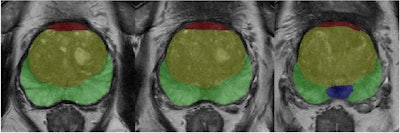

Example of prostate zonal segmentation by the AI software in a patient. Yellow = transition zone; green = peripheral zone; red = anterior fibromuscular stroma; and blue = central zone.Shang et al; Insights into Imaging

In a retrospective single-center study, the research team used AI software to automatically measure both prostate and zonal volumes and calculate PSAD and TZ-PSAD for 606 patients who underwent transrectal ultrasound-guided systematic biopsy after negative MRI imaging.

The AI system was used for accurate and reproducible segmentation and measurement of the prostate zones, the authors added.

The following four prostate zones were measured: transition zone volume (TZV), peripheral zone volume (PZV), central zone volume (CZV), and anterior fibromuscular stroma volume (AFSV).